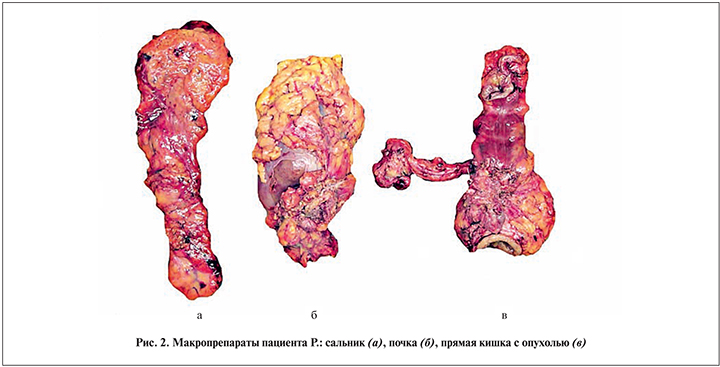

01.03.2018 пациент был прооперирован. В связи с выраженным спаечным процессом после предыдущей операции выполнен адгезиовисцеролизис. По передней поверхности нижнего полюса левой почки определялся плотный узел диаметром 4,4 см, прораставший в почку и боковую стенку живота. Второй узел размерами 3×3 см располагался в полости малого таза, прорастал в верхнеампулярный отдел прямой кишки, вовлекая семенные пузырьки с обеих сторон, семявыносящий проток справа и прилегал к правому мочеточнику в области его устья. Была проведена мобилизация оставшихся левых отделов ободочной кишки, поперечной ободочной кишки, левой почки. В связи с тем что не представлялось возможным исключить инвазию опухолевого узла в левую почку, было решено выполнить не ее резекцию, а нефрэктомию. Осуществлена мобилизация прямой кишки до нижнеампулярного отдела вместе с опухолевым узлом и вовлеченными с обеих сторон семенными пузырьками, правым семявыносящим протоком. В процессе мобилизации в связи с прилежанием опухолевого узла к правой стенке таза проведена перевязка внутренней подвздошной артерии в месте отхождения от общей подвздошной артерии. Ободочная кишка была пересечена проксимальнее ранее сформированного трансверзосигмоидного анастомоза на 1 см, прямая – на уровне среднеампулярного отдела, на 5 см дистальнее нижнего полюса опухоли. После этого макропрепарат единым блоком удален из брюшной полости. В левой мезогастральной области сформирована одноствольная трансверзостома. Таким образом, больному была выполнена комбинированная ререзекция левых отделов ободочной кишки, прямой кишки по Гартману, резекция семявыносящих протоков и двусторонняя везикулэктомия, нефроуретерэктомия слева с резекцией боковой стенки живота, одноствольная трансверзостомия (рис. 2, 3).

Гистологическое исследование удаленного препарата показало, что в прямой кишке имелась метахронная опухоль, имеющая строение умеренно дифференцированной аденокарциномы с глубоким изъязвлением, очагами некроза, периваскулярным и периневральным ростом с врастанием в брюшину, семенные пузырьки и окружающую их клетчатку, обрастанием семявыносящего протока с очаговым врастанием в его стенку. В 3 параректальных из 19 исследованных лимфатических узлах определены метастазы аденокарциномы с полным замещением лимфоидной ткани, очагами инвазии опухоли за капсулу узлов. Узел, вовлекший почку, расположен в основном экстраренально, был представлен опухолевой тканью аналогичного строения опухоли прямой кишки с врастанием в капсулу и паренхиму нижнего полюса почки и наличием опухолевых эмболов в ее сосудах. Сосуды ворот почки и мочеточник были интактными. Также определено врастание опухолевого узла в резецированные участки скелетных мышц передней брюшной стенки с инвазией сосудов.